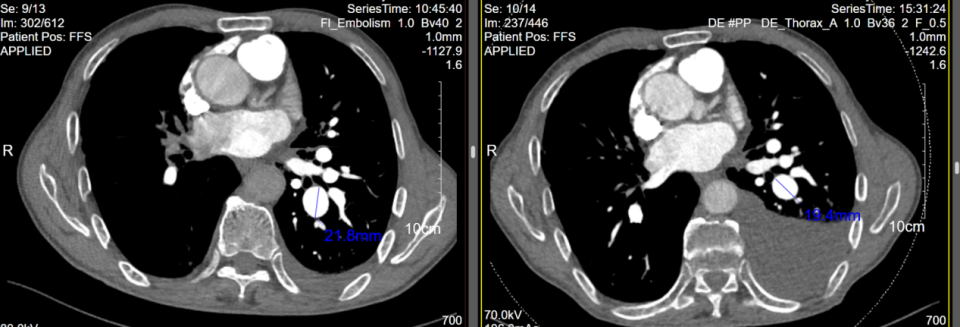

患者于2025年9月15日行右心导管检查+超选择性肺动脉造影+肺动脉分支球囊扩张术+肺动脉支架植入术。术中测肺动脉压力 46/11 (23) mmHg,热稀释法测量心输出量约3.0L/min,肺血管阻力6 Wood单位。超选择性肺动脉造影提示多支肺动脉狭窄闭塞,右侧A8-A10肺动脉共干狭窄90%以上,狭窄部位最大扩张直径为6mm,植入10 x 40 mm支架1枚后因狭窄严重,支架缩入远端,后植入10 x 60 mm支架1枚覆盖重叠,再予7.0 x 40 mm球囊后扩,扩张至6 ATM患者再次出现咳嗽,遂结束手术,术后压力导丝测量下FFR约0.68(术中影像见图6)。术后诊断:1.毛细血管前肺动脉高压(2022ESC/ERS诊断标准);2. 肺动脉狭窄。

患者于2025年10月14日再次回心血管内科门诊随访,复查肺动脉CTA可见仍有左侧胸腔积液,但胸水量较前有所减少,同时右肺下叶动脉狭窄处复通,左下肺动脉扩张处直径较前缩小(见图7)。根据患者自述,他目前咳嗽减少,无胸闷、气促表现,无需进行胸腔积液引流。但因患者经济条件欠佳,暂不行肺静脉的造影和介入处理,继续观察。

图6:右肺动脉分支介入治疗前后

图7:2025.08.18与术后2025.10.14CTPA对比